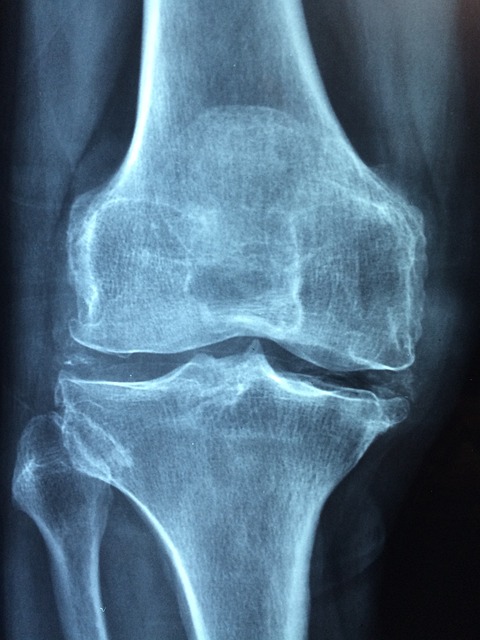

성상철 의학박사는 무릎 인공 관절 수술은 수술 2~3개월 후면 통증이 많이 없어지고 정상적인 생활이 가능해져서 환자들이 매우 만족해한다고 합니다. 최근 미국에서는 1년에 100만 명, 우리나라에서도 1년에 10만 명 정도의 퇴행성 관절염 환자가 인공 관절 수술을 받고 있으며, 대부분 연령이 65세가 넘는 분들이라고 합니다. 우리나라 의학 수준은 세계 최고의 수준으로 수술 환자의 만족도가 90~100% 가까운 안전하고 보편적인 수술이라고 하는대요. 연령이 많을수록 수술에 대한 두려움이 클 수도 있지만 큰 질병만 없으면 수술 후 회복 하는데 큰 문제가 없어 가벼운 운동이나, 사회적 활동이 가능하다고 합니다.